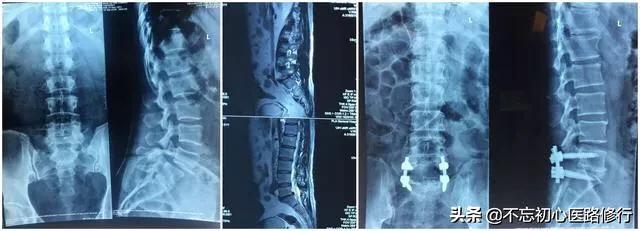

Pourquoi existe-t-il deux approches chirurgicales ?

En effet, lorsqu'une hernie discale est retirée, une partie de la stabilité entre les vertèbres est perdue, ce qui peut entraîner des douleurs lombaires et une dégénérescence accélérée du dos. Ainsi, pour les patients plus âgés, qui ont déjà un dos instable, il est possible de subir une chirurgie de fusion unique, qui consiste à retirer tous les disques, à placer un dispositif de fusion et à fixer le dos à l'aide d'une fixation interne. Les risques de cette procédure sont plus importants que l'ablation seule ; en effet, la procédure comporte plus d'étapes et prend plus de temps.

Avec l'approche chirurgicale traditionnelle, plus l'incision chirurgicale est grande, meilleure est la ligne de vue et meilleur est l'espace opératoire.

Elle convient aux hernies discales lombaires multisegmentaires, à forte compression et plus complexes. Si l'on exclut les risques chirurgicaux, les soi-disant échecs chirurgicaux possibles sont le descellement de la fixation interne, le retrait et la non-cicatrisation de l'incision. C'est rarement le cas.

Avantages : élimination complète de la lésion.

Inconvénients : grandes incisions et traumatisme.